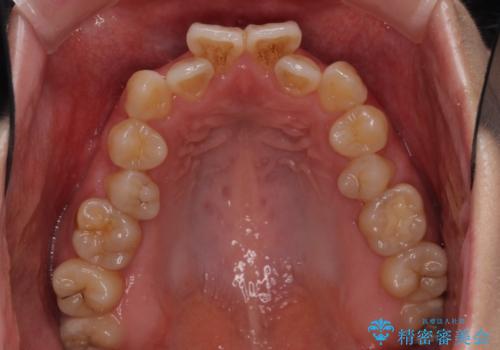

- 前歯の反対咬合を気にして来院された患者様です。

目立ちにくい装置での治療をご希望とのことで、上顎が裏側装置、下顎が表側装置のハーフリンガルにより矯正治療を行うこととしました。